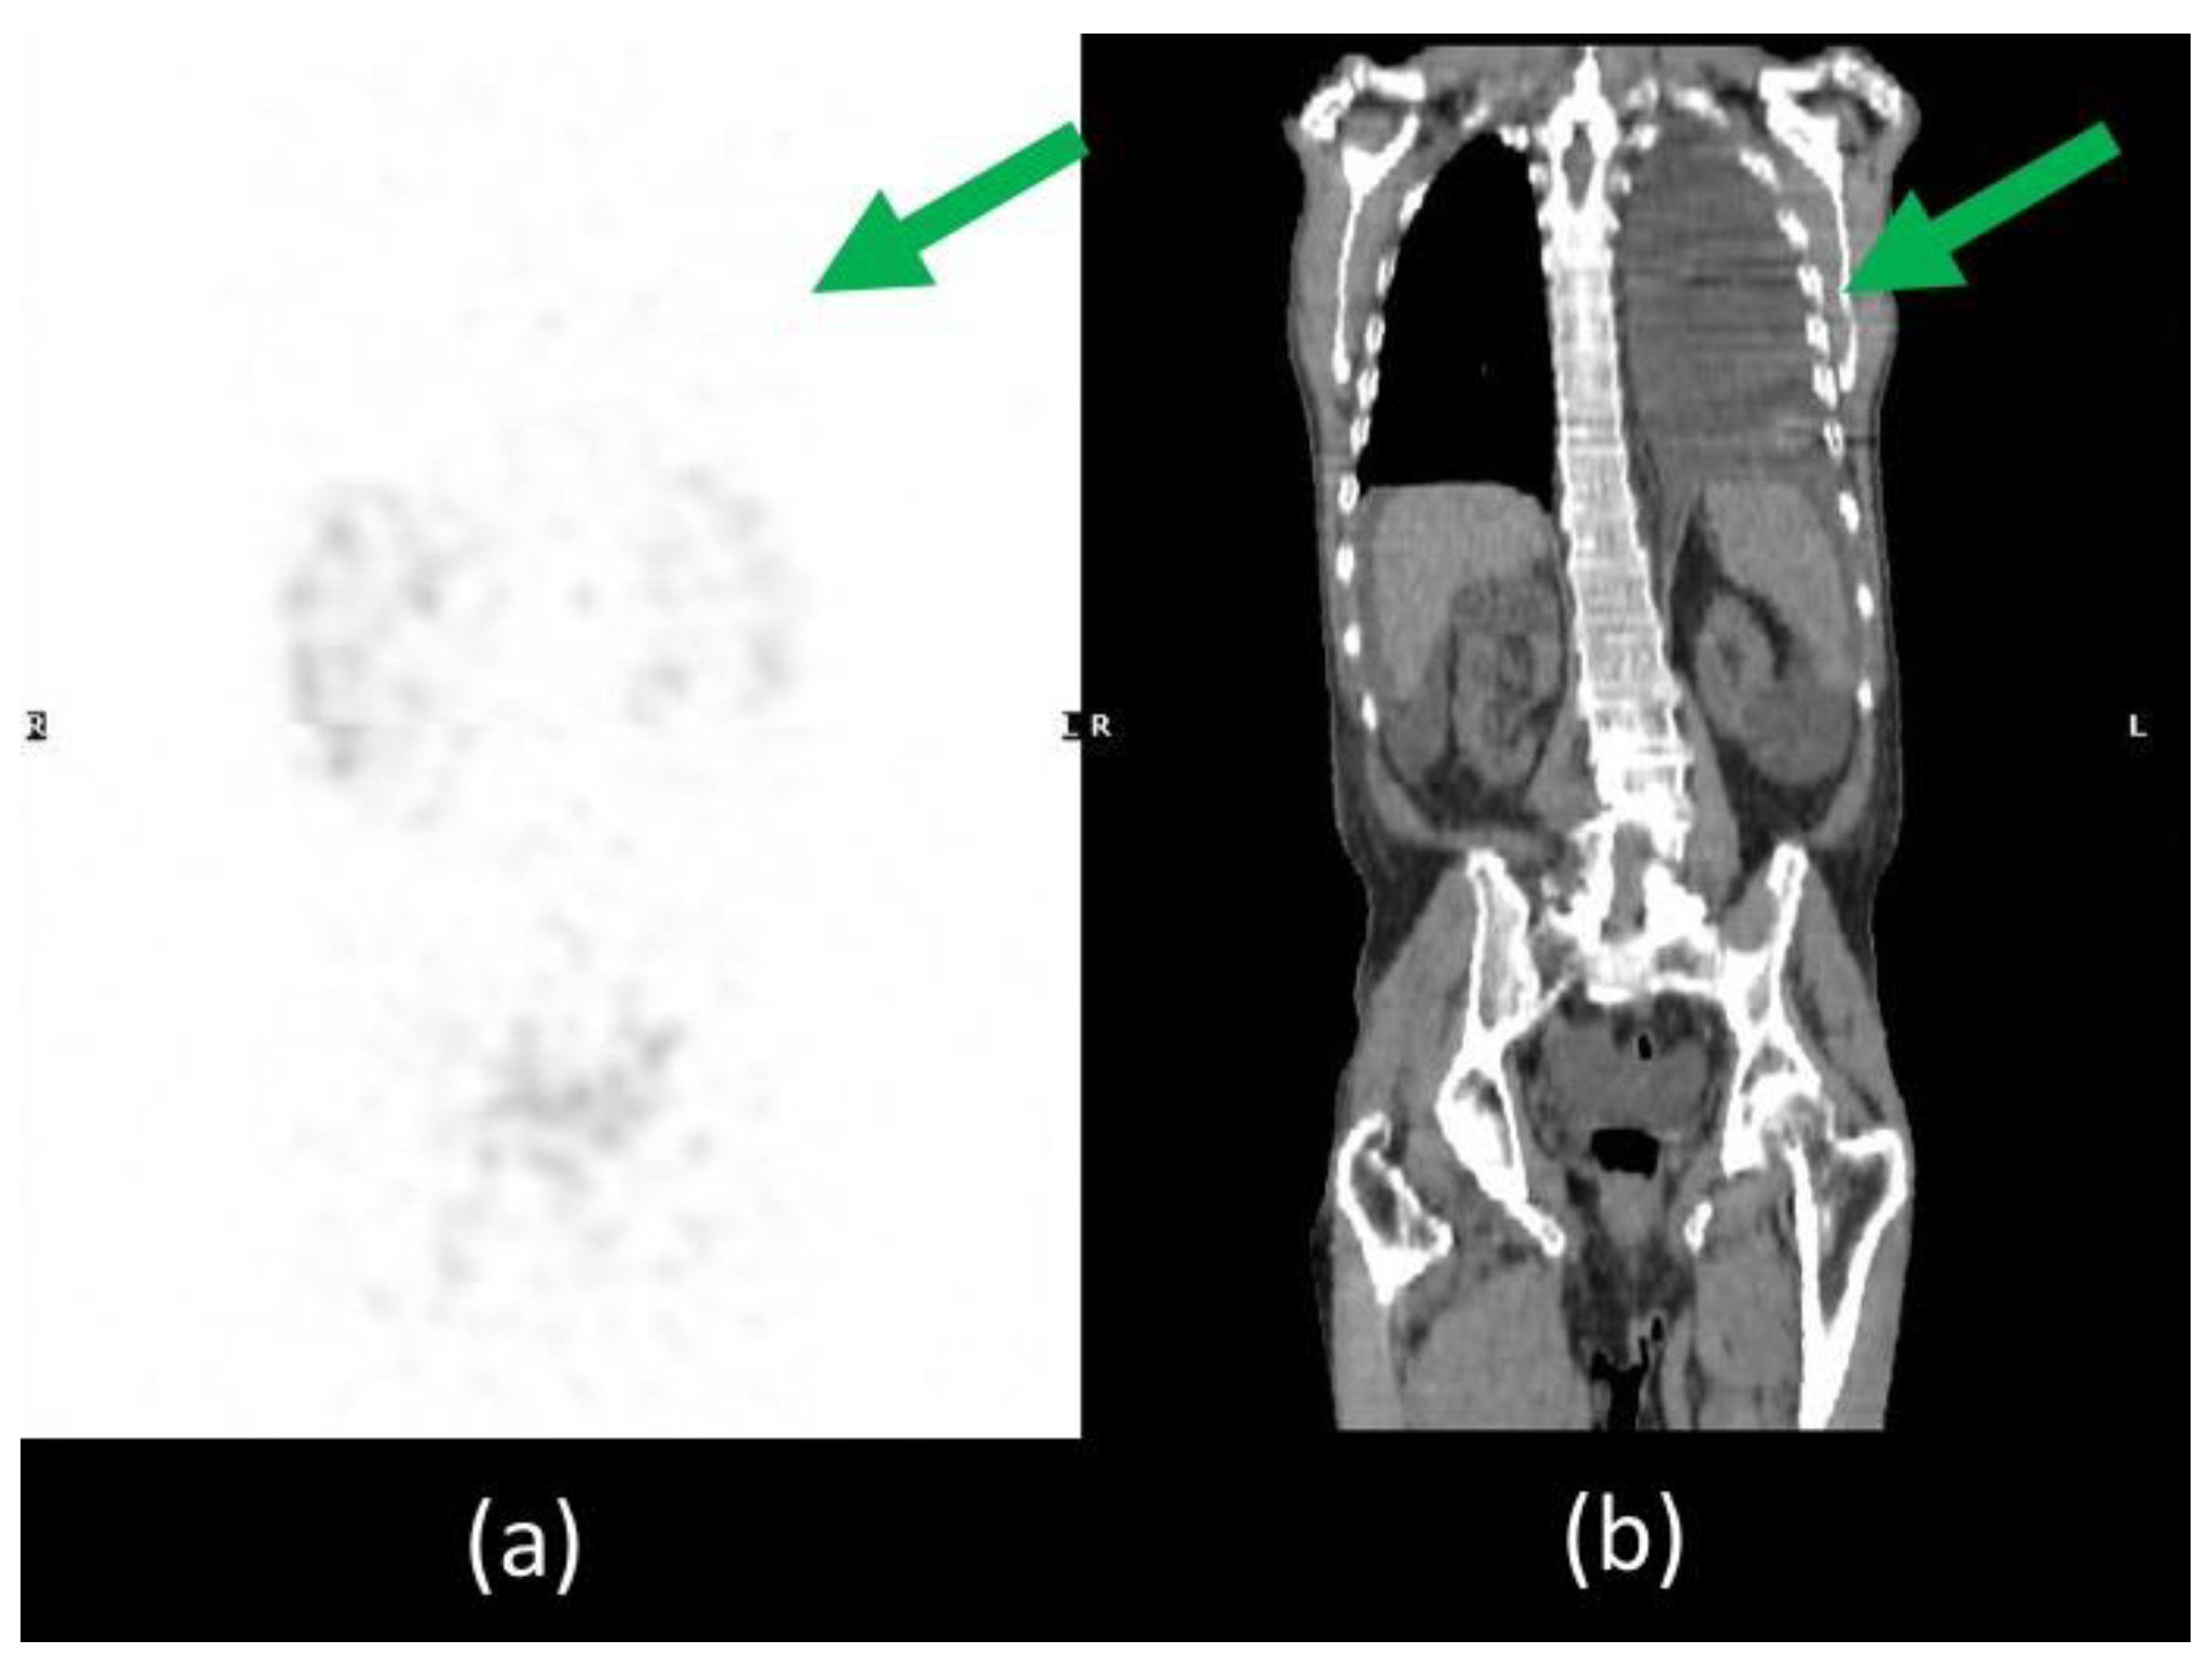

Furthermore, thorax SPECT/CT did not show radioactivity distribution in the left pleural effusion excluding the presence also of chylothorax and demonstrating its reactive aetiology of it (Figure 5).

Figure 5.

SPET/CT whole body lymphoscintigraphy. MIP image (a) did not show any radiotracer uptake in the left pleural effusion visible on CT coronal image (b), excluding the presence of chylothorax (green arrow).